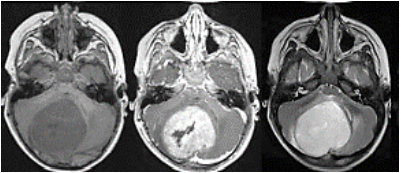

Encaminhado a um pronto socorro pediátrico aonde foi submetido a ressonância nuclear magnética (RNM – figura 3):

Figura 3 RNM de crânio

Assinale a alternativa correta a respeito do quadro da paciente.